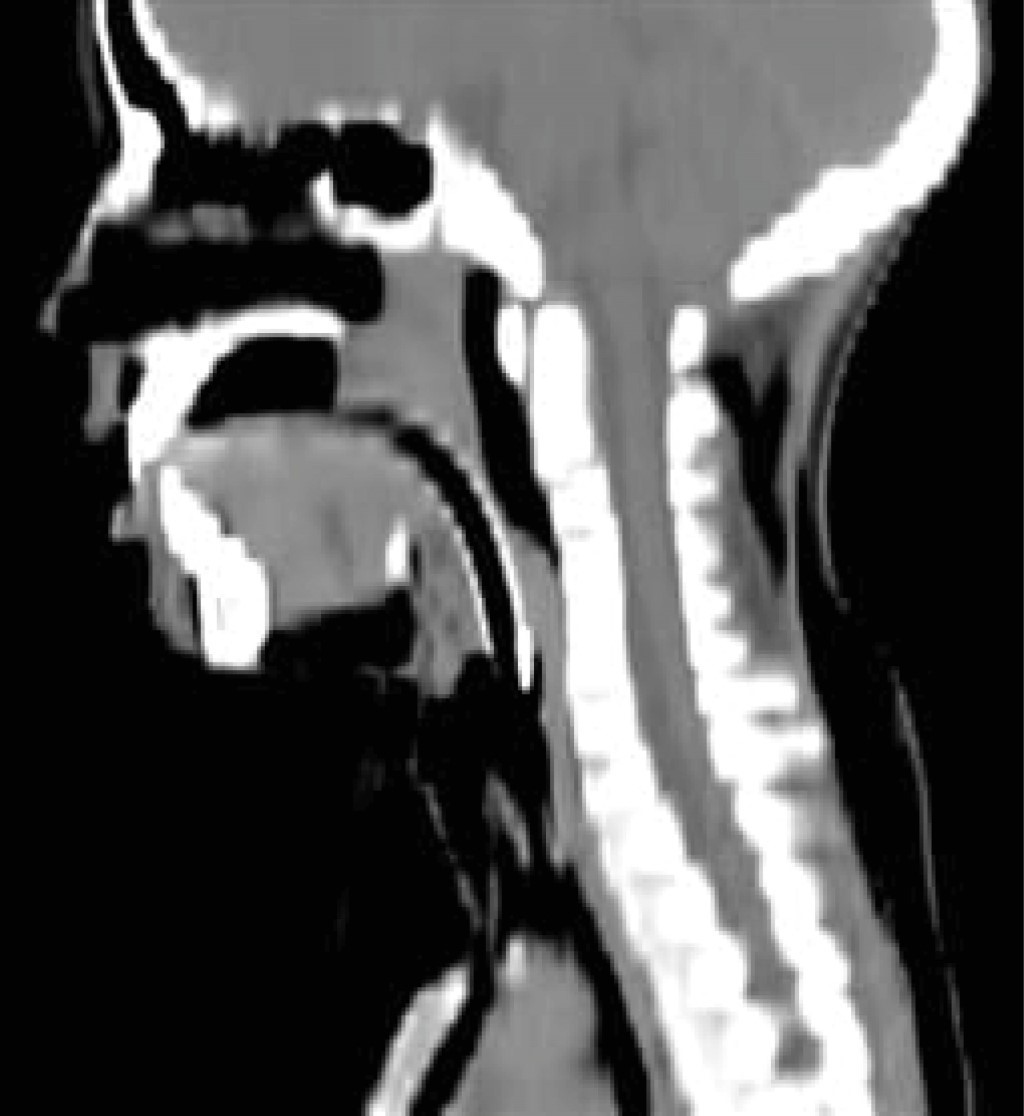

Simultaneous management of shock and pneumothorax was initiated, involving bilateral thoracostomy tube placement with subsequent water seal drainage, which effectively achieved drainage. Given the presence of circumferential ecchymosis and abundant blood clots, a post-intubation fibrobronchoscopy was performed to investigate suspected airway injury. Computed axial tomography (CT) revealed tracheal widening at the C7 level, consistent with an anterior traumatic lesion of the trachea (Figure 1).

Figure 1